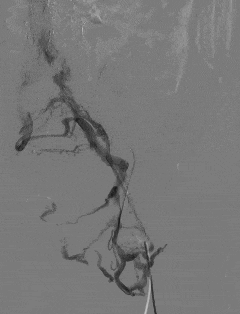

手术过程中,田轩团队凭借精湛的介入技术,经大隐静脉入路穿刺,成功开通闭塞的髂静脉。

术中造影进一步确认,李叔叔左下肢深静脉全程闭塞,血流无法正常回流。

团队随即采用球囊扩张导管逐级对闭塞血管进行精准扩张,逐步恢复血管管腔通畅性。

术后即时评估显示,左下肢髂静脉恢复部分血流,肢体回流障碍得到有效改善。